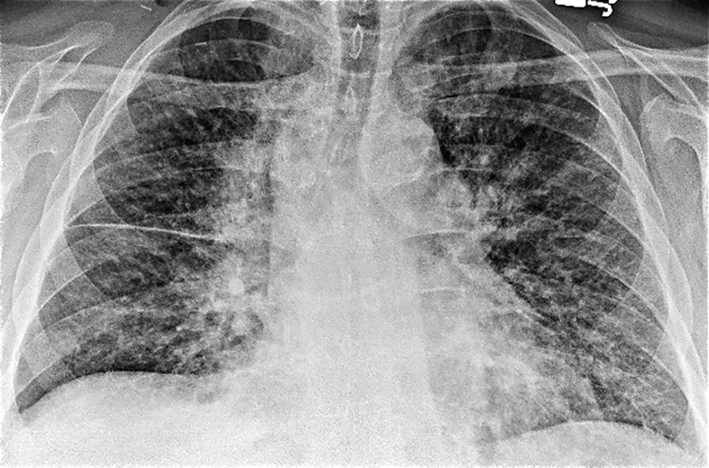

Laboratory studies were significant for anemia with hemoglobin at 11 (12 - 15.5 g/dL) and leukocytosis with WCC 15.41 (3 - 11 × 103 mL). His creatinine was 0.67 (0.3 - 1.2 mg/dL) and B natriuretic peptide level was within normal limit at 53 (0 - 99 pg/mL). Chest X-ray showed bilateral perihilar haziness, consistent with pulmonary edema (Fig. 1). His electrocardiogram revealed sinus tachycardia with right bundle branch block. An echocardiogram demonstrated a good left and right ventricular systolic function (left ventricular ejection fraction 59%), grade-1 diastolic dysfunction with trivial tricuspid regurgitation. A diagnosis of diastolic heart failure was considered and patient was treated with diuretics, aiming daily negative fluid balance of 500 - 1,000 mL. He had lost 2 kg of weight since admission within a week with improvement of his pedal edema. However his breathing continued to deteriorate even after aggressive diuresis. On the seventh day of admission, he became tachypneic and hypoxic with arterial blood gas showing hypoxic and hypercarbic respiratory failure (pH 7.28, pO2 78 mm Hg and pCO2 76 mm Hg on FIO2 of 1.0). A repeat chest X-ray revealed diffuse bilateral infiltrates, predominantly interstitial in character, worsened compared to previous chest X-ray (Fig. 2). He required intubation and support with mechanical ventilation. Patients CT scan of chest (Fig. 3) demonstrated mediastinal lymphadenopathy, diffuse pulmonary nodules, multifocal infiltrates worse in right upper lobe, lower lobe, lingular lobe, and left lower lobe as well as bilateral pleural effusion.

![]() Click for large image | Figure 1. Chest X-ray on admission showed bilateral perihilar haziness and fluid in right transverse fissure consistent with pulmonary edema. |